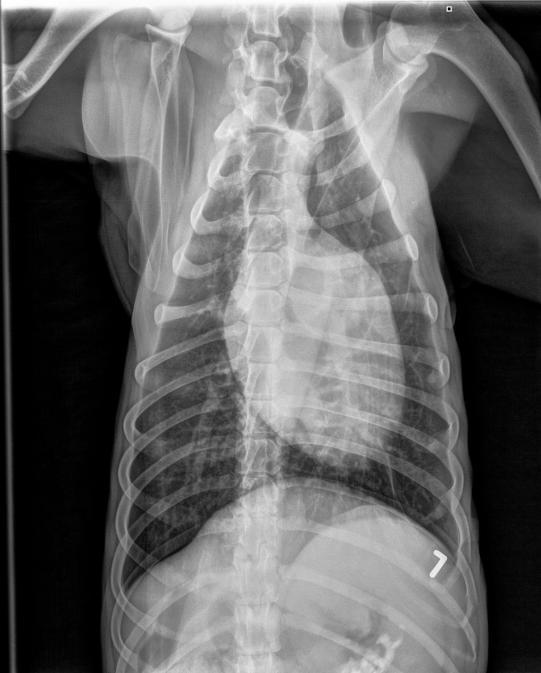

Nun geht es der Hündin glücklicherweise langsam besser, und 10 Tage später wird das Tier nochmals geröntgt: Die Lungenentzündung hat sich komplett zurückgebildet - allerdings lässt sich im Ultraschall aber auch keine Trächtigkeit feststellen.